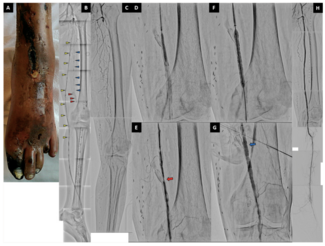

Hiroto Tamura, MD; Shingo Kurimoto, MD; Kenichiro Yuba

A 57-year-old woman with critical limb-threatening ischemia (CLTI) of the left lower leg underwent endovascular therapy. She had undergone a femoropopliteal (F-P) bypass for treatment of chronic total occlusion (CTO) of the superficial...